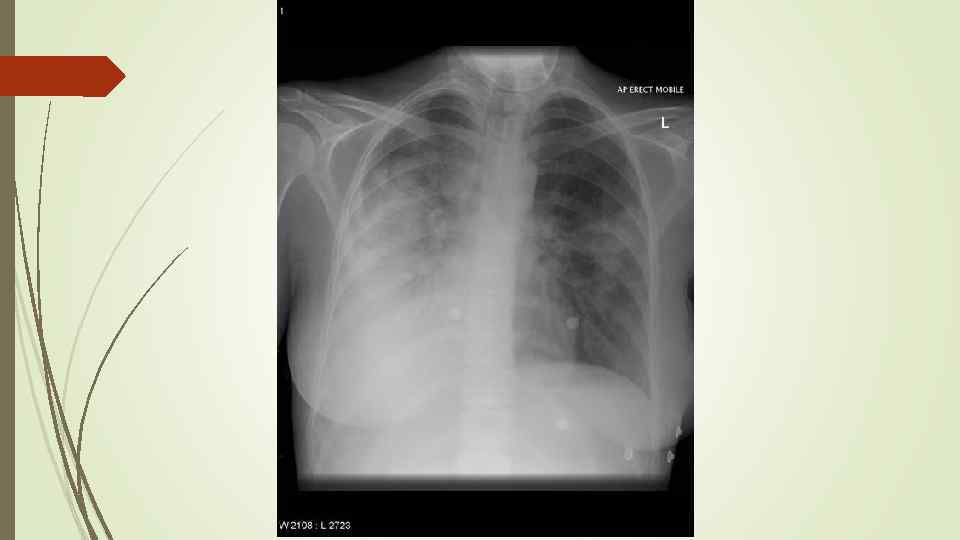

Бронхопневмония Характерно наличие двухсторонних множественных очаговых теней. Контуры очагов нечеткие, интенсивность тени небольшая. Инфильтрация неоднородна. Мелкие, малоинтенсивные очаги не всегда выявляются на снимках. Легочный рисунок усилен на всем протяжении легких. Корни расширены, не структурны. Как правило, отмечается реакция плевры, могут быть и экссудативные плевриты.

Бронхопневмония Характерно наличие двухсторонних множественных очаговых теней. Контуры очагов нечеткие, интенсивность тени небольшая. Инфильтрация неоднородна. Мелкие, малоинтенсивные очаги не всегда выявляются на снимках. Легочный рисунок усилен на всем протяжении легких. Корни расширены, не структурны. Как правило, отмечается реакция плевры, могут быть и экссудативные плевриты.